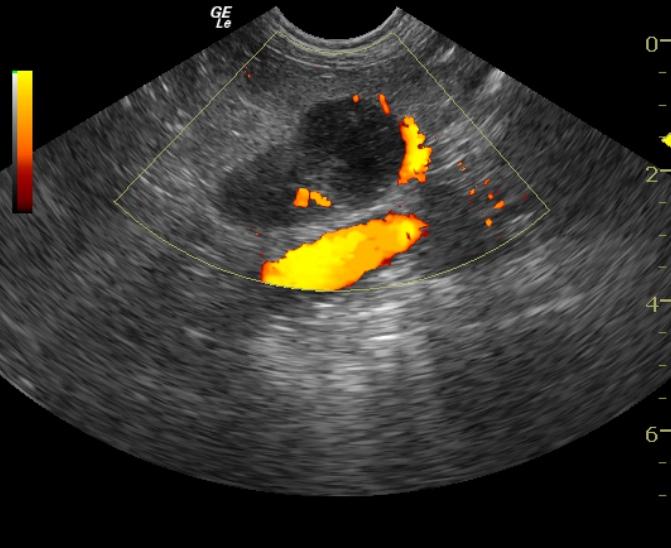

A 15-year-old FS mixed breed dog was presented for alopecia. On physical exam, her hair was found to be sparse and in patches along her dorsum. She was also mentally dull and appeared to be disoriented. Bilateral cataracts were present and there was a mild increase in the intraocular pressure measured bilaterally (tonometry measurement of 21 mm Hg). Blood chemistry revealed hyperphosphatemia, elevated ALT, elevated AST, and elevated GGT enzyme activities. The CBC, urinalysis, urine microalbumin, T4 and TSH were all within normal limits.

A 15-year-old FS mixed breed dog was presented for alopecia. On physical exam, her hair was found to be sparse and in patches along her dorsum. She was also mentally dull and appeared to be disoriented. Bilateral cataracts were present and there was a mild increase in the intraocular pressure measured bilaterally (tonometry measurement of 21 mm Hg). Blood chemistry revealed hyperphosphatemia, elevated ALT, elevated AST, and elevated GGT enzyme activities. The CBC, urinalysis, urine microalbumin, T4 and TSH were all within normal limits. A chemistry profile was repeated and showed persistence of the hyperphosphatemia, increased liver enzymes (ALT, AST, GGT) and hyperglobulinemia.